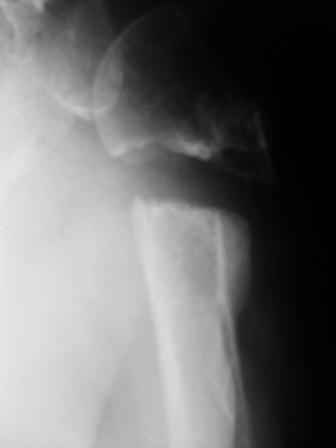

ложный сустав плеча

Уважаемые коллеги! Госпитализирована больная 51года. Травма - перелом хирургической шейки плеча в феврале 2009г.

Лечилась по месту жительства Лонгетной гипсовой повязкой. На фоне сформировавшегося ложного сустава работает маляром. Объем движений и сила естественно ограничены. При обсуждении тактики лечения возникли разногласия по поводу вида остеосинтеза и его целесообразности.